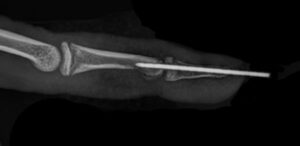

- U nekim slučajevima dolazi do koštanog preloma (slika 2).

Osnova postavljanja dijagnoze je u kliničkom pregledu. Zbog mogućnosti prisustva koštane lezije čije prisustvo može uticati na plan daljeg lečenja potrebno je uraditi i rendgenski snimak povredjenog prsta.

Ukoliko postoji i povreda kosti (avulzioni prelom) naš lični stav je da je najbolje uraditi fiksaciju fragmenta K iglom koja će se nositi narednih 6-8 nedelja.